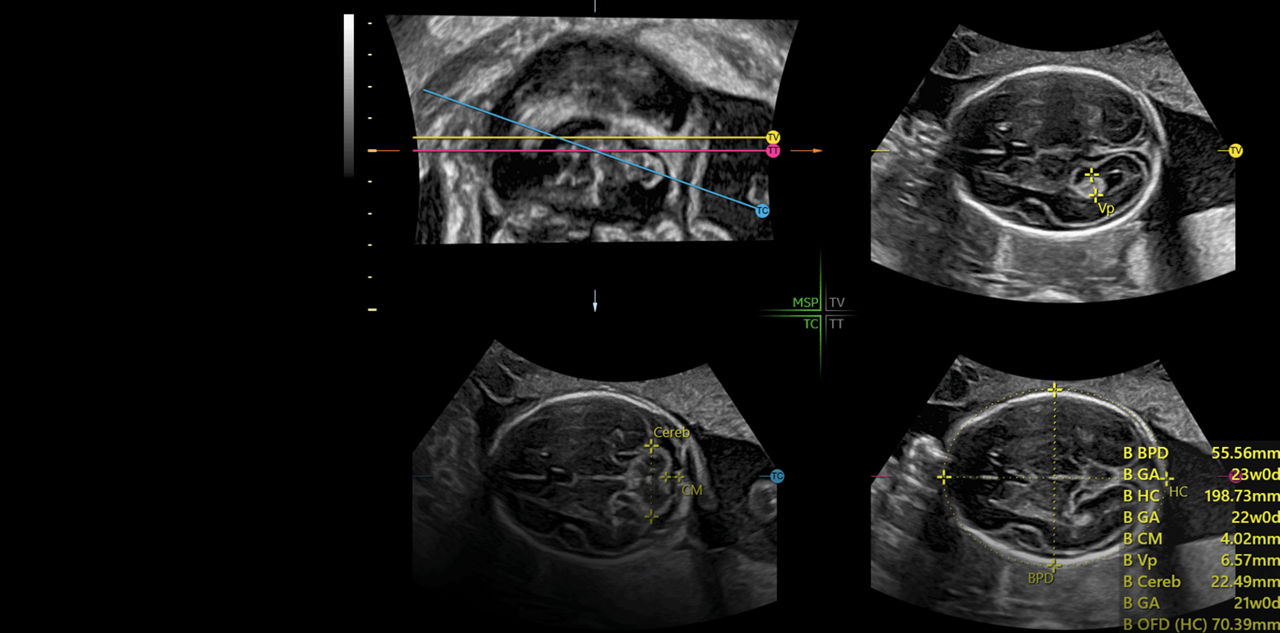

Amplify imaging performance and simplify scanning with our most advanced architecture

Extraordinary clarity and definition so you can focus on early detection and intervention.

Faster.Sharper. Clearer.

Faster.Sharper. Clearer.